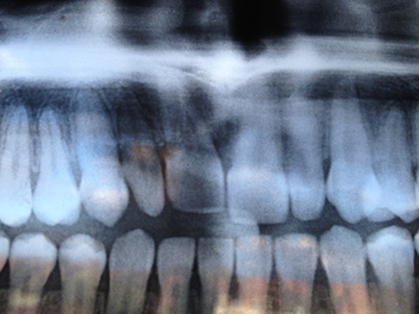

Panoramique dentaire sans particularité .

Aspect normal .Migration symétrique de 11 et 21. Aucune anomalie endondontique ou parodontale

Espace clair périapical de 11 bien visible. Aucune résorption endodontique

Espace clair périapical de 11 , fin régulier, très bien visible. Symétrie parfaite. Aucune anomalie endodontique. Absence de clarté kystique pericoronaire de 13 dont on note la clarté centrale régulière